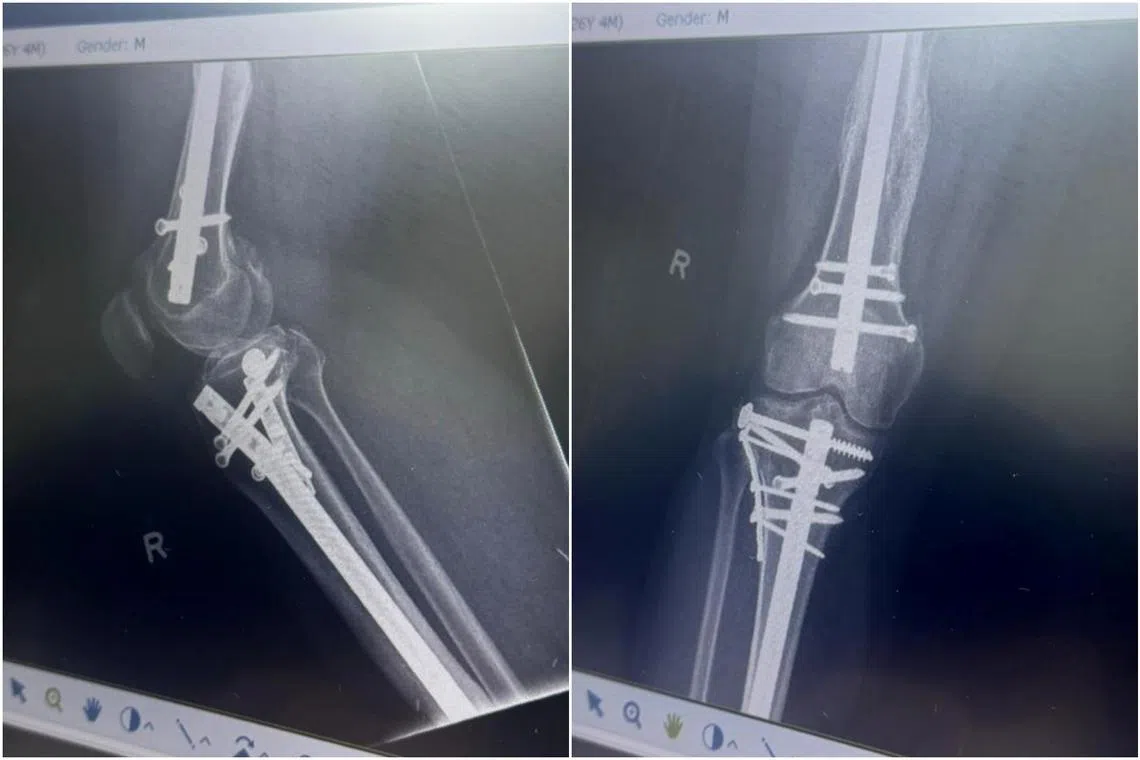

He now has a metal rod in his right leg and multiple screws in his neck and shoulders.

X-rays showing injuries and metal screws in Mr Mahmud’s right leg after he was crushed between two cars in the December 2021 accident.

PHOTOS: COURTESY OF MR MAHMUD AZMANI FIKRI